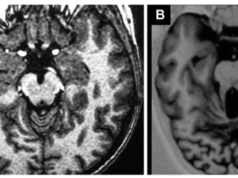

Schizencefalia

Schizencefalia - afecțiune neurologica determinată de o dezvoltare anormală a creierului ce apare între prima și a șaptea lună de gestație. Simptome: microcefalie, macrocranie cu hidrocefalie, paralizii ale membrelor, întârziere în dezvoltarea psihică, convulsii, care în 80% din cazuri apar sub vârsta de 3 ani.